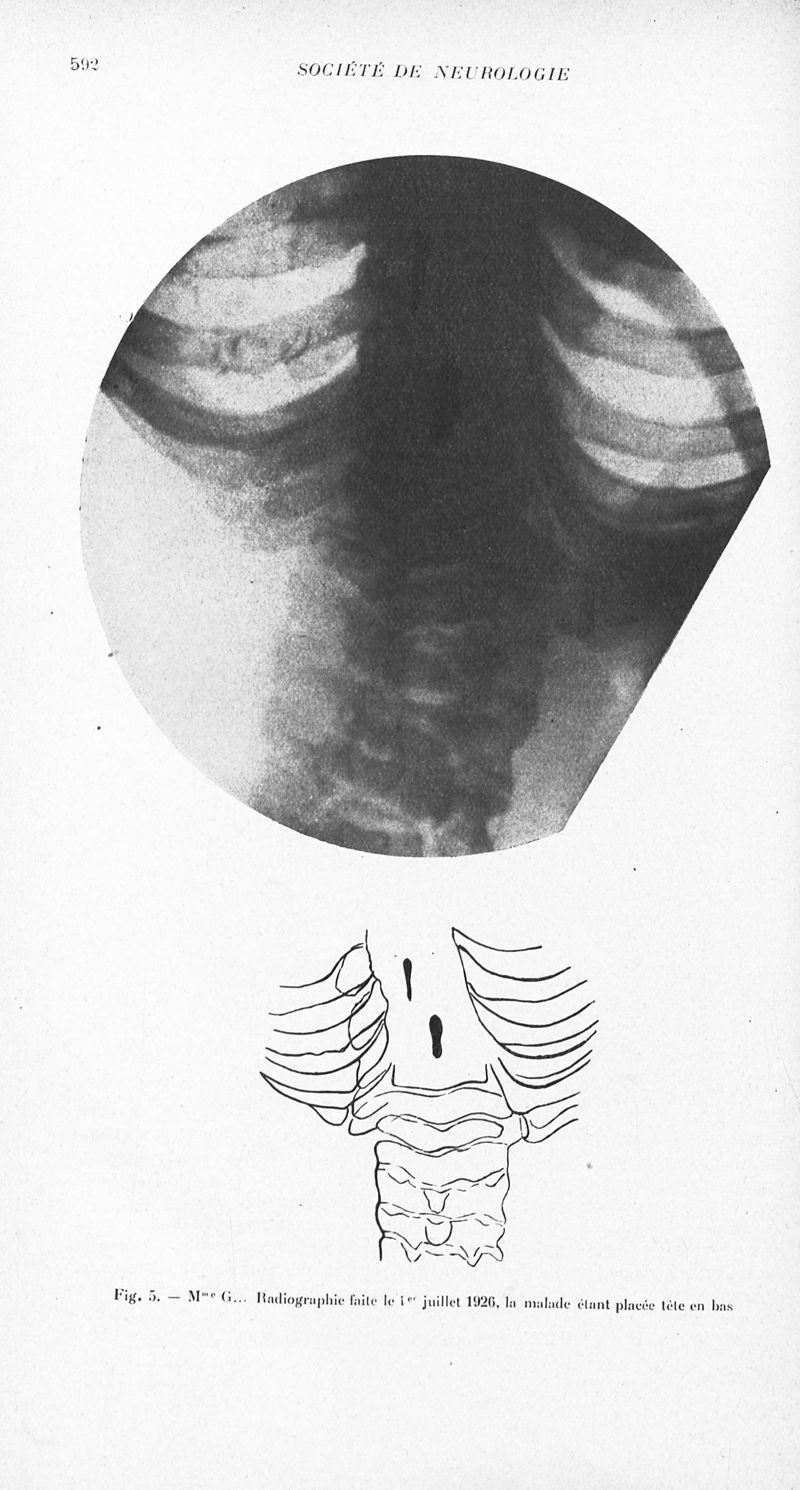

1926, vol 2. - Paris : Masson , 1926.